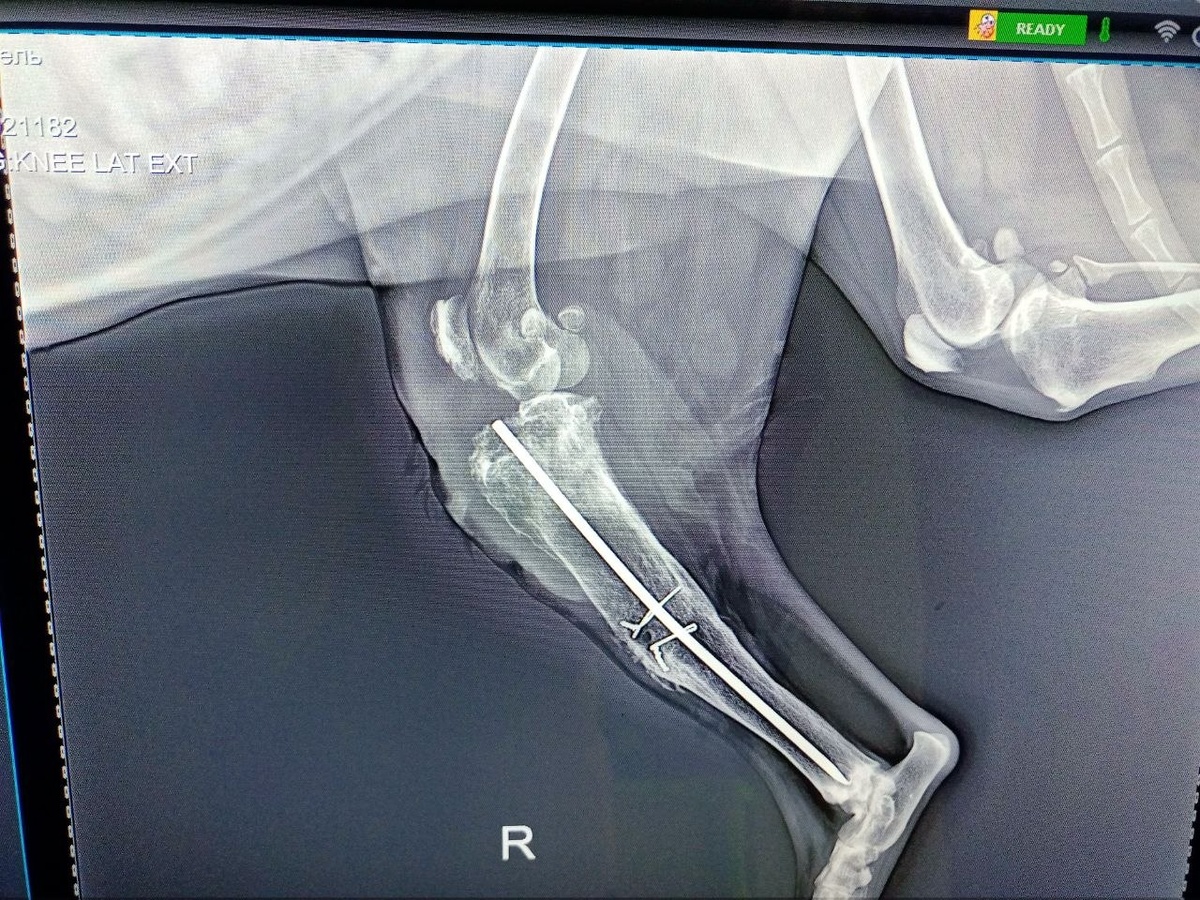

На рентгене оказалось, что когда-то Рашель была сделана операция и в лапу вставлена спица с проволокой. Что произошло не ясно, у Рашель нет соседей по проживанию и навредить ей не могли, но спица сдвинулась и вылезла.

Рашель срочно готовят к операции, есть шанс спасти лапу, но надо вытащить конструкцию.